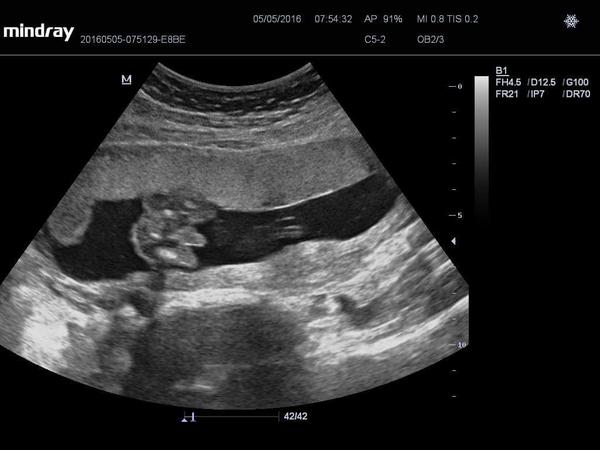

@xjanikka ano je to stoprocentně chlapeček

@barbucha123 Chlapeček 🙂